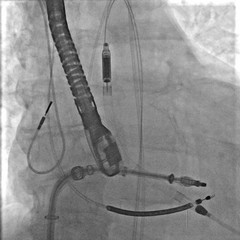

È accaduto presso il Bonomo di Andria, per la prima volta in Puglia, è stato eseguito su un paziente 62enne un complesso intervento combinato di riparazione trans catetere di mitrale con il supporto del sistema di assistenza ventricolare Impella, che funge da pompa microassiale intravascolare per supportare temporaneamente la funzione cardiaca, del ventricolo sinistro, in caso di grave sofferenza o shock cardiogeno.

"A causa della severa disfunzione della contrattilità cardiaca - spiega il dott. Claudio Larosa, cardiologo emodinamista che ha eseguito l'intervento - anche l'intervento trans catetere avrebbe comportato notevoli rischi procedurali. Si è, pertanto, pianificata la riparazione della valvola mitralica trans catetere con utilizzo contemporaneo di un sistema di assistenza ventricolare sinistra. Tale dispositivo, chiamato Impella, è stato posizionato all'interno del cuore attraverso un accesso arterioso di grosso calibro ad ha avuto l'obiettivo di supportare la funzione del cuore, severamente compromesso durante l'intera durata della procedura interventistica, evitando che il paziente potesse scompensarsi. L'intervento è stato portato a termine con successo ed il paziente è stato estubato e risvegliato già a fine procedura ed è stato trasferito, in buone condizioni, in terapia intensiva cardiologica dove è stato prontamente assistito dal personale di reparto".

"Questo complesso intervento combinato di riparazione trans catetere di mitrale con il supporto del sistema di assistenza ventricolare Impella, mai eseguito prima in Puglia - prosegue il dott. Francesco Bartolomucci - ha consentito di intervenire in sicurezza e con pieno successo in un contesto clinico molto complesso. L'insufficienza della valvola mitralica è una patologia cardiaca con un'alta prevalenza. Si stima, infatti, che circa il 10% della popolazione di età uguale o superiore a 75 anni ne sia affetto. L'incompleta chiusura dei lembi mitralici causa un flusso di sangue retrogrado che, se non trattato, può portare alla congestione del ciclo polmonare, allo scompenso cardiaco ed alla disfunzione della funzione cardiaca. Le forme severe, se non trattate, sono associate ad una seria compromissione della qualità di vita".